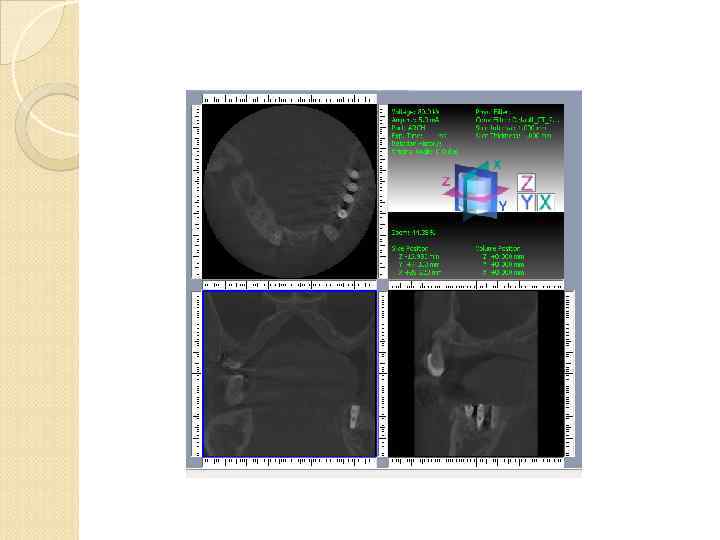

Однако для визуализации всех необходимых анатомических структур, выявления анатомо-топографических особенностей и патологических процессов челюстей вышеперечисленных методов рентгенографии бывает недостаточно рентгенограмма является двухмерным суммационным изображением и не позволяют исследовать объекты в

Однако для визуализации всех необходимых анатомических структур, выявления анатомо-топографических особенностей и патологических процессов челюстей вышеперечисленных методов рентгенографии бывает недостаточно рентгенограмма является двухмерным суммационным изображением и не позволяют исследовать объекты в

вследствие обязательных проекционных искажений, обусловленных технологией получения рентгенограмм, сложно произвести точные измерения.

вследствие обязательных проекционных искажений, обусловленных технологией получения рентгенограмм, сложно произвести точные измерения.

У пациентов с дефектами зубных рядов при подготовке к имплантации ортопантомограммы не всегда позволяют точно оценить степень атрофии альвеолярных отростков в различных плоскостях, четко рассчитать расстояние от альвеолярного гребня до важных анатомических образований

У пациентов с дефектами зубных рядов при подготовке к имплантации ортопантомограммы не всегда позволяют точно оценить степень атрофии альвеолярных отростков в различных плоскостях, четко рассчитать расстояние от альвеолярного гребня до важных анатомических образований

Спиральная компьютерная томография СКТ дает больше диагностической информации по сравнению с обычной КТ. Возможна реконструкция изображения в любой заданной плоскости Спиральные компьютерные томографы оснащены специальной программой «Dentascan» в различных вариантах. По данным аксиального изображения каждой из челюстей строится кривая, проходящая через центр альвеолярного отростка

Спиральная компьютерная томография СКТ дает больше диагностической информации по сравнению с обычной КТ. Возможна реконструкция изображения в любой заданной плоскости Спиральные компьютерные томографы оснащены специальной программой «Dentascan» в различных вариантах. По данным аксиального изображения каждой из челюстей строится кривая, проходящая через центр альвеолярного отростка

Все типы стандартных программ сложны в применении, без специальной подготовки оператора. Лучевая нагрузка 400 мк. Зв Затруднительно построение кривой через середину альвеолярного гребня с учетом различной степени деформации и толщины кортикальной

Все типы стандартных программ сложны в применении, без специальной подготовки оператора. Лучевая нагрузка 400 мк. Зв Затруднительно построение кривой через середину альвеолярного гребня с учетом различной степени деформации и толщины кортикальной

Специализированные стоматологические томографы для сканирования вместо тысяч точечных детекторов используется один плоскостной сенсор. генерируемый луч коллимируется в виде конуса. рассчитаны на детальное исследование костной ткани и твердых тканей зубов Мягкие ткани

Специализированные стоматологические томографы для сканирования вместо тысяч точечных детекторов используется один плоскостной сенсор. генерируемый луч коллимируется в виде конуса. рассчитаны на детальное исследование костной ткани и твердых тканей зубов Мягкие ткани